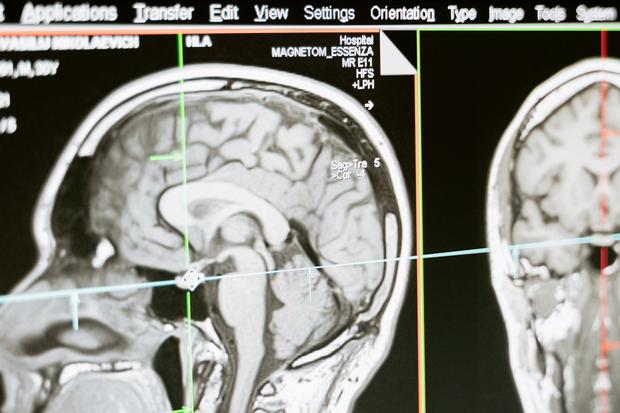

Casi uno de cada cuatro participantes (24%) experimentó hinchazón y edema en el cerebro, y tres pacientes murieron como resultado. Por lo tanto, el tratamiento debe controlarse, por ejemplo mediante exámenes periódicos de resonancia magnética (MRI). “En última instancia, se necesitarán más datos para determinar si los riesgos de estos medicamentos superan sus modestos beneficios clínicos”. El comentario de JAMA sobre el estudio dice.

Es útil hacerse un análisis de sangre confiable en el que se extrae sangre y luego se analiza en un laboratorio. Esto es exactamente lo que pretende hacer el conjunto actual de investigaciones sobre la enfermedad de Alzheimer. Además de las pruebas de memoria, el diagnóstico de la enfermedad se basa actualmente en análisis del líquido cefalorraquídeo (LCR) y tomografías por emisión de positrones (PET) para detectar Abeta y tau. Esto es complejo, costoso y muy estresante para los pacientes. Un buen análisis de sangre debería ayudar a identificar tempranamente a las personas que podrían beneficiarse de un tratamiento preventivo.